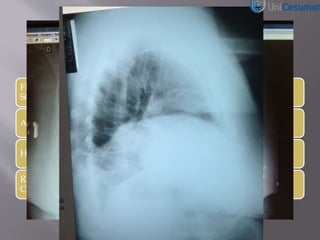

Radiografia

(1) Pneumoperitônio

Radiografia em ortostase pode detectar

Pneumoperitônio de 1ml1

Radiografia em decúbito lateral esquerdo pode

detectar 5 a 10 ml de ar sob a parede abdominal2

RX TORAX ELEVAÇÃO CUPULA DIAFRAGMATICA DIREITA

COM CONDENSAÇÃO PULMONAR OU PNEUMOPERITONEO?